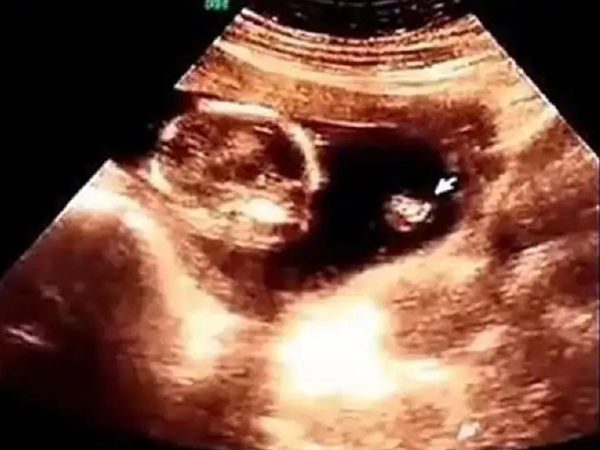

2、男孩三条线:怀男孩一般是出现三个亮点,因此如果B超图像中出现了很短的三条线,且在男孩的双腿之间的话,是怀男孩的特征,由此可以判断出胎儿性别是男孩的可能性更大。

男孩三条线示例